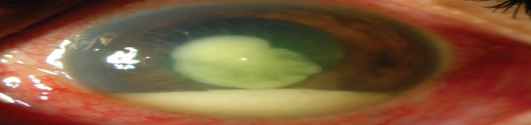

Hypopyon collection of WBCs in the anterior chamber.

causes : bacterial keratitis , ant. Uveitis

Bacterial keratitis Signs and symptoms

Severe pain, purulent discharge, ciliary injection (flush), visual loss( if the visual axis is involved), hypopyon(a mass of WBCs collected in the anterior chamber), white corneal opacity

Bacterial keratitis clincial info

-3 serious findings: hypopyon, ciliary flush, corneal cloudiness